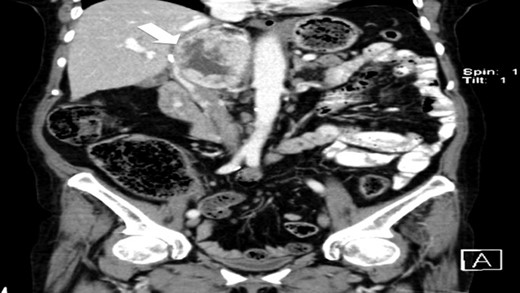

The authors report a case of a 64-year-old female, with no relevant family history and a past medical history of recently diagnosed supraventricular tachycardia, arterial hypertension, type 2 diabetes mellitus, euthyroid multinodular goiter and chronic venous insufficiency. She was referred to our Institution from other Hospital where she went due to paroxysms of palpitations, headache and diaphoresis, that led to biochemical investigation that was remarkable for: total plasmatic cathecolamines: 73 747 ng/L (normal range (NR) <598 ng/L), plasmatic noradrenaline: 73 589 ng/L (NR <420 ng/L), adrenaline: 130 ng/L (NR <84 ng/L), plasmatic dopamine: 28 ng/L (NR <94ng/L), aldosterone: 87,5 ng/dL (NR 4–31 ng/dL), plasmatic renin activity: 33 ng/mL/h (NR 0,5–4 ng/mL/h), Vanylmandelic acid: 39,2 mg/24 h (NR <13,6 mg/24 h). Abdominal contrast enhanced CT scan revealed a large (70 × 35×78 mm3), hyperdense (20 HU) right adrenal mass. Abdominal magnetic resonance (MRI) also described an adrenal mass with 66×33 mm2, suggestive of pheocromocitoma (slightly hypointense on T1 and markedly hyperintense on T2 weighted imaging). No vascular nor locoreginal lymph node involvement were found and the left adrenal was radiologically normal. The patient underwent genetic testing with next generation sequencing, that excluded mutations of the succinate dehydrogenase (SDHB, C, D and A), MEN2, VHL, Neurofibromatosis type 1 genes. Genetic testing for MAX and TMEM127 were not performed due to institutional unavailability. Pre-operative pharmacological therapy was initiated with phenoxybenzamine (10 mg twice a day), followed by bisoprolol (20 mg/day) and amlodipine (5 mg/day), which rendered the patient fit for surgery. The patient underwent transperitoneal laparoscopic right adrenalectomy. Intraoperatively, a hipervascularized right adrenal gland with adhesions to the upper pole of the kidney was identified and excised, with no complications recorded. In the immediate post-operative period, antihypertensive drugs were stopped and blood pressure remained normal until the second post-operative day, when hypertension and tachycardia recurred, leading to urinary metanephrine reevaluation on the 10th post-operative day. The results were highly suggestive of disease persistence (urinary normetanephrines >10 500 ng/L (NR <600 ng/L)). Histology revealed no signs of neoplasia. Abdominal CT scan revealed the persistence of a solid heterogeneous nodule, with 70 × 49 × 87 mm3 (AP × T × L) adjacent to upper right renal pole, with peripheral contrast enhancement and central necrosis (Figs 1–3). This findings suggested abdominal paraganglioma (of the organ of Zuckerkandl). Due to the higher malignant potential of paragangliomas, an 123I-MIBG scintigraphy was performed, excluding metastatic disease.

CT scan (coronal) of the heterogenous solid nodule adjacent to upper inner right renal pole (white arrow).